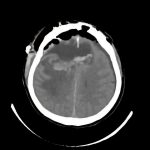

症例 '16年6月

No.

年_番号

手術年月

患者年齢

’16_80

'16年6月

70代

病名

術式

備考

髄膜腫

(大脳鎌)

断層撮影

手術前

1

手術前2

手術後